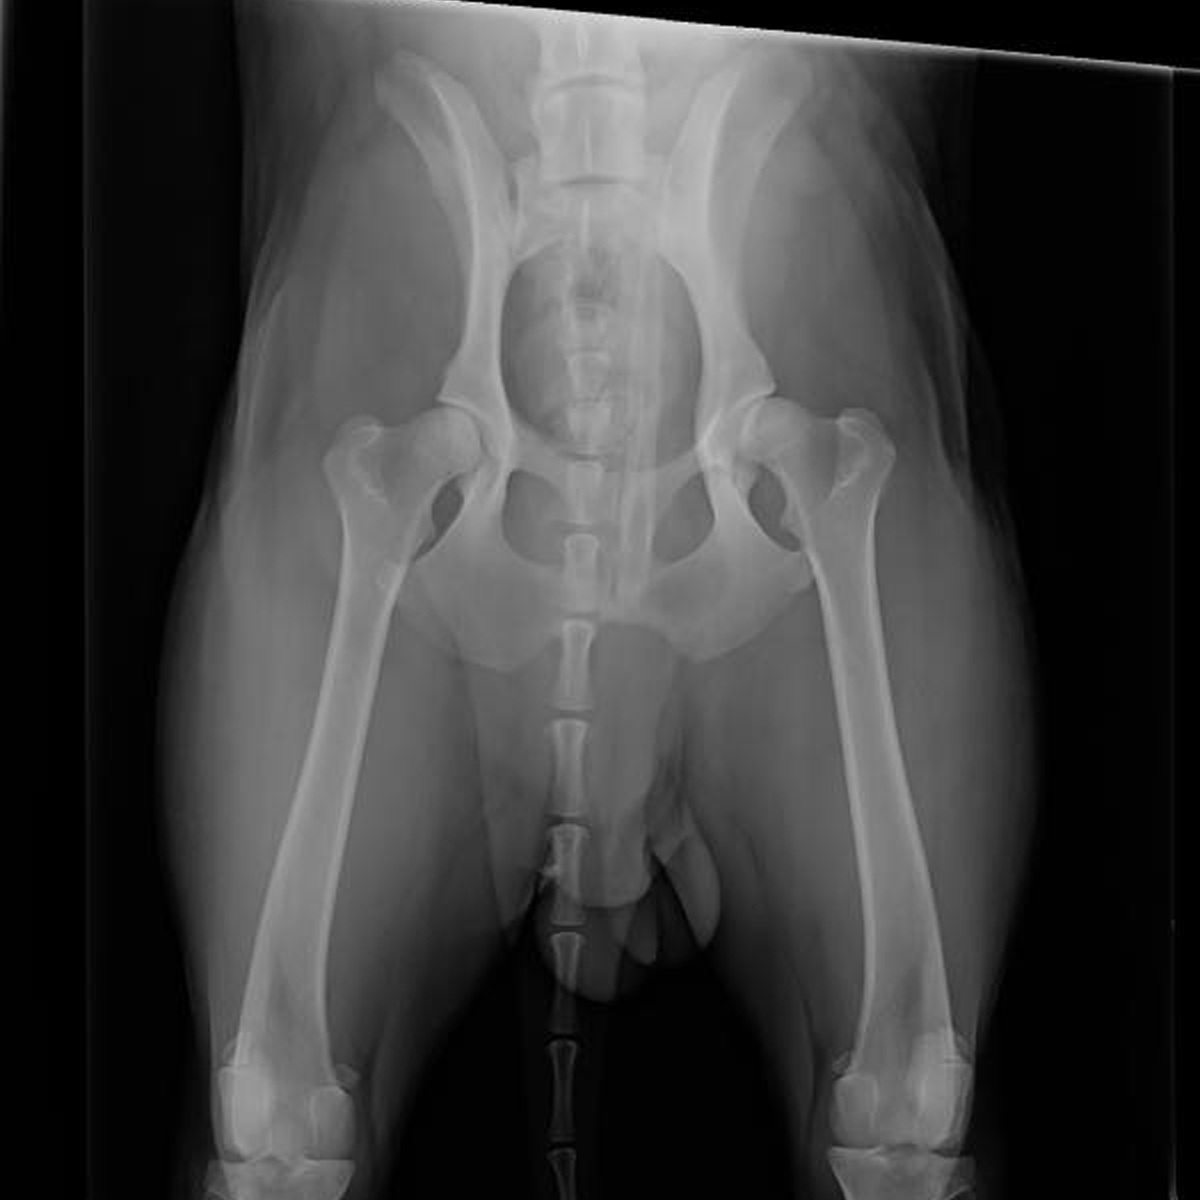

X-Rays (Radiographs)

Our hospital is fully equipped to take high-quality radiographs (often called X-rays) of your pet. These images are an important diagnostic tool that helps our veterinarians examine areas of the body we can’t see during a physical exam. X-rays are especially useful for identifying problems involving bones, the chest, or abdomen, such as fractures, arthritis, foreign objects, or organ changes.